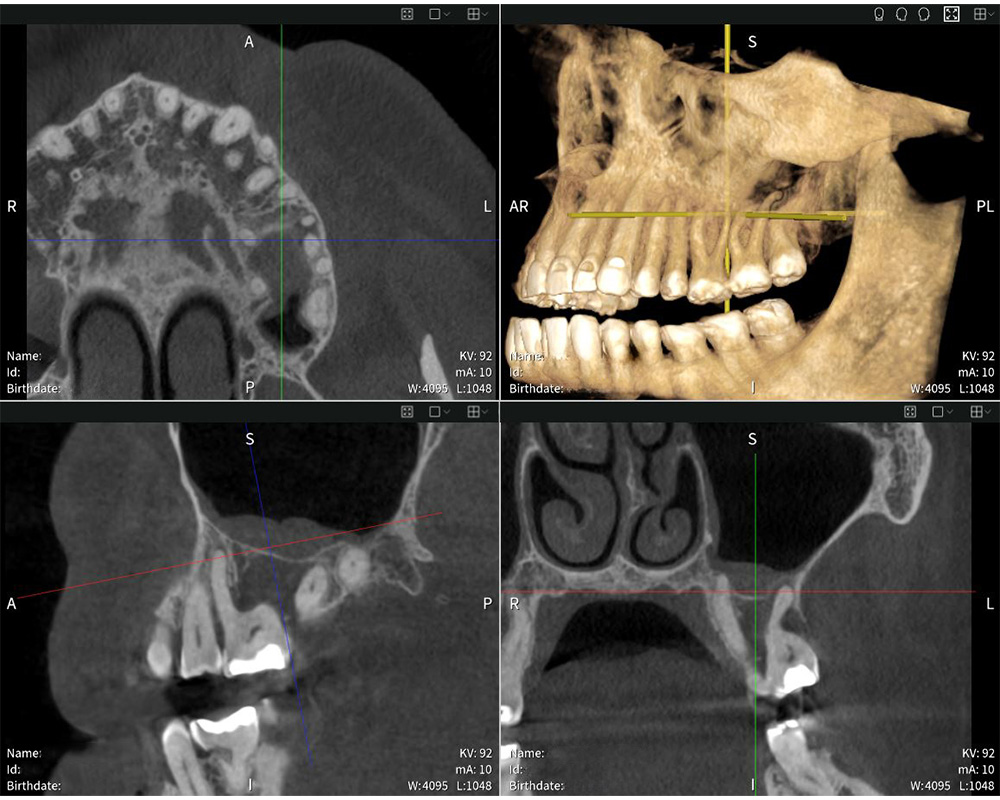

Seethrough Studio ensures sharp, detailed, and undistorted images.

Seethrough Studio ensures sharp, detailed, and undistorted images. © W&H

Highly precise imaging results with Seethrough Max: the X-ray shows the swelling of the mucosa in the sinus maxillaris.

Highly precise imaging results with Seethrough Max: the X-ray shows the swelling of the mucosa in the sinus maxillaris. © Dr med. dent. Mauro Amato